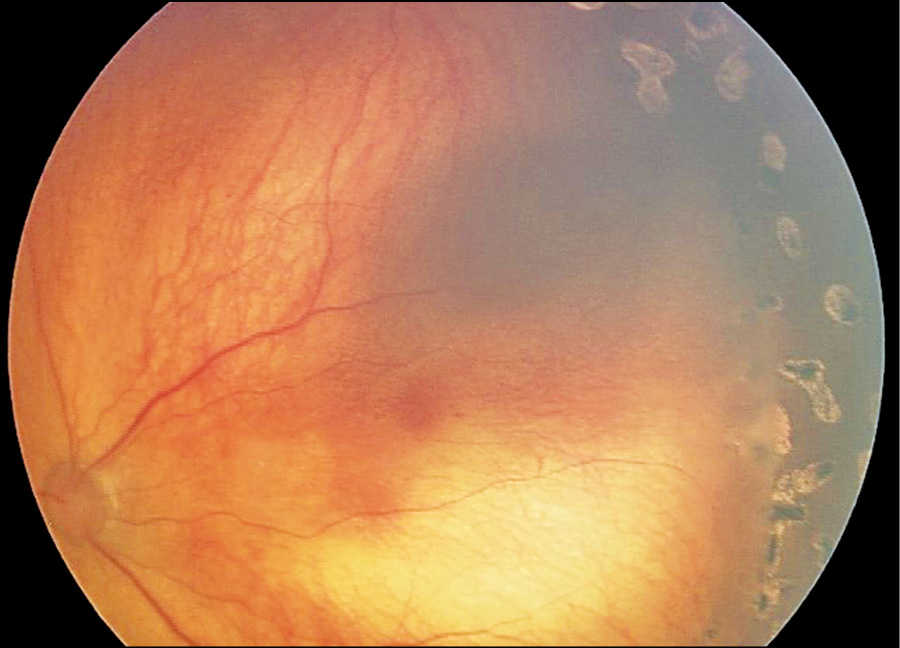

В возрасте 1 года 11 месяцев родители самостоятельно обратились в СПб ГБУЗ «Детский городской многопрофильный клинический центр высоких медицинских технологий им. К.А. Раухфуса» для планового обследования на предмет исключения РВ единственного глаза. С учётом отягощенного анамнеза обследование и фоторегистрация изображений проводились с помощью RetCam более чем в 5 стандартных позициях: центр, нижний, верхний, назальный и темпоральный отделы. Выявлен единичный очаг РБ на периферии глазного дна левого глаза, а через 5 дней — второй очаг (рис. 4). Была диагностирована ретинобластома группы А левого глаза и совместно с онкологами сразу назначено комбинированное органосохраняющее лечение.

Рис. 4. Очаги ретинобластомы на периферии глазного дна левого глаза.

Fig. 4. Retinoblastoma foci on the periphery of the fundus of the left eye.

Второй клинический пример свидетельствует о вероятности развития опухоли на здоровом глазу спустя более 1,5 лет после первичной энуклеации глаза с РБ. Рассмотренный случай подтверждает необходимость регулярного динамического офтальмологического контроля (каждые 3 месяца в течение года; каждые 6 месяцев в течение 2-го и 3-го года; далее 1 раз в год пожизненно). По возможности следует использовать педиатрическую ретинальную камеру для фоторегистрации патологических изменений с целью сохранения функционирующего органа зрения.